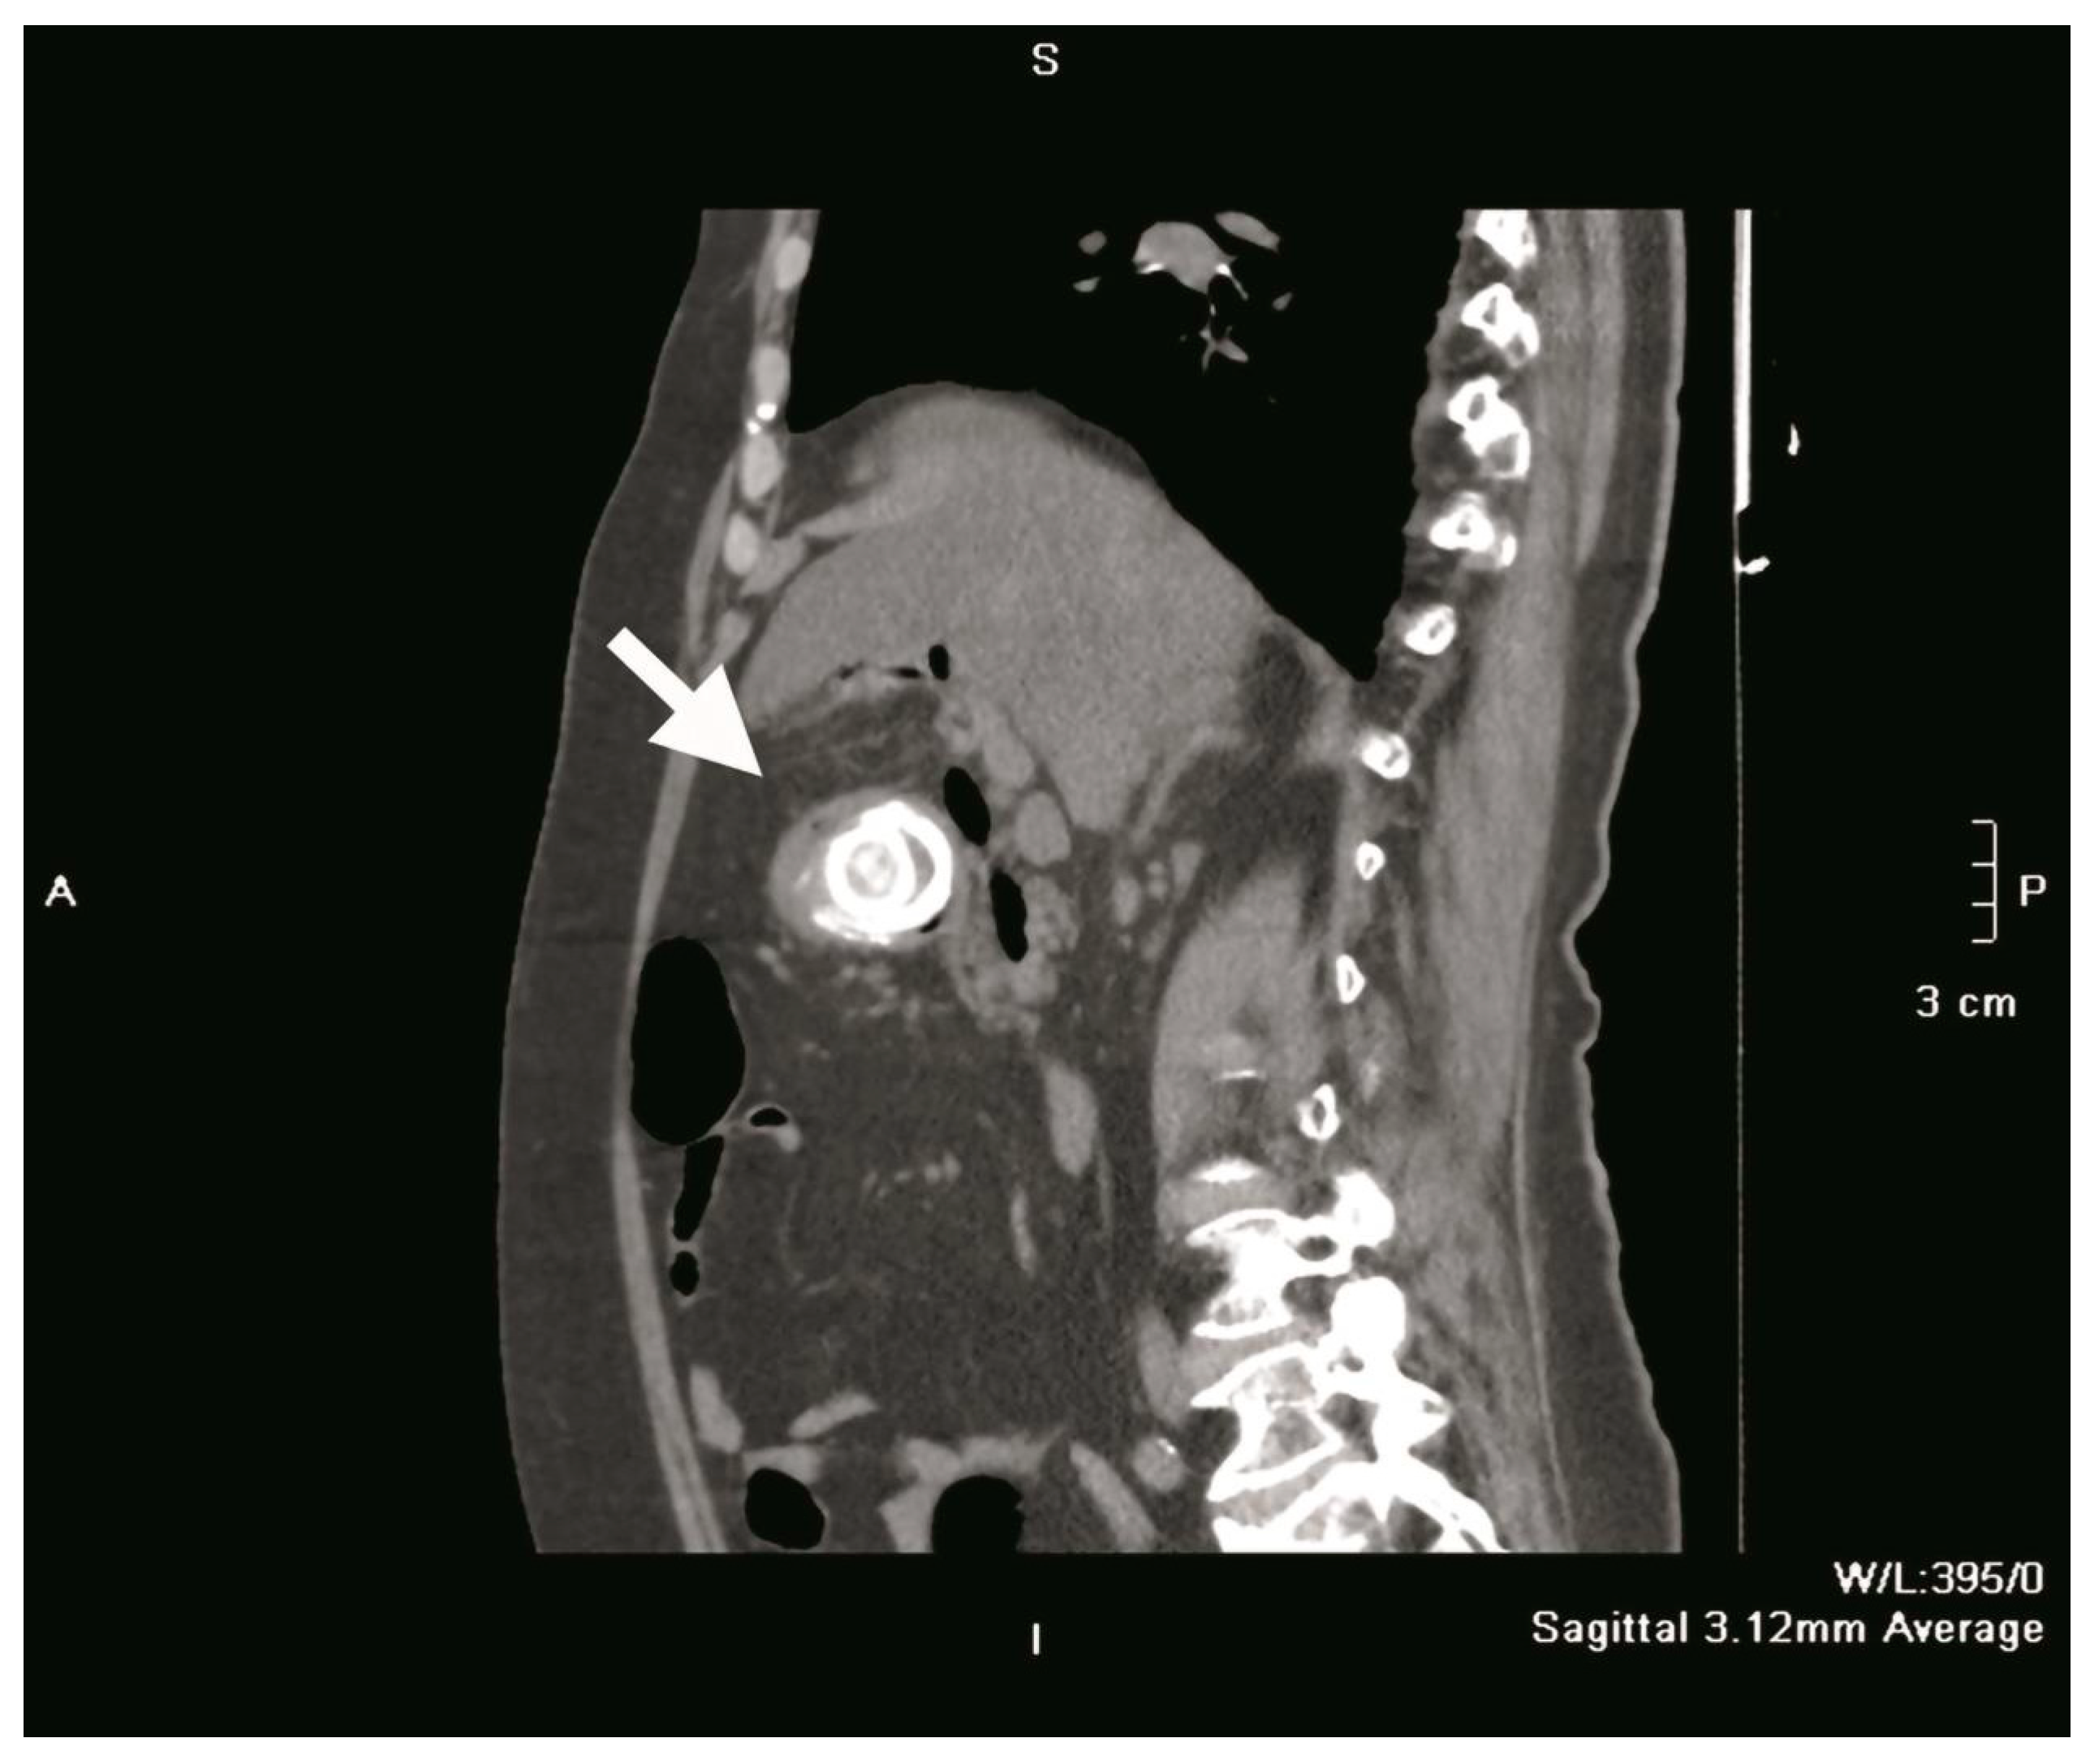

Plain abdominal radiography revealed a distended, fluid-filled stomach with signs of pneumoperitoneum (a result of gallbladder perforation; however, there was no secondary peritonitis because the process was blocked by the greater omentum) and obstruction. A 4 cm shadow of calcium intensity was noted in the right lumbar region. Abdominal ultrasonography demonstrated a partially distended, thick-walled gallbladder with multiple calculi, a finding consistent with chronic cholecystitis. Follow-up contrast-enhanced abdominal CT confirmed the presence of a cholecysto-duodenal fistula in the first part of the duodenum, with a 3.9 cm × 4.0 cm × 4.0 cm gallstone lodged in the proximal duodenum (Figure 1 and Figure 2). The scan also revealed sludge and calculi in the gallbladder, along with a distended, fluid-filled stomach and aerobilia.

Figure 2.

Sagittal section CT scan showing a gallstone (white arrow) impacted in the duodenal bulb.